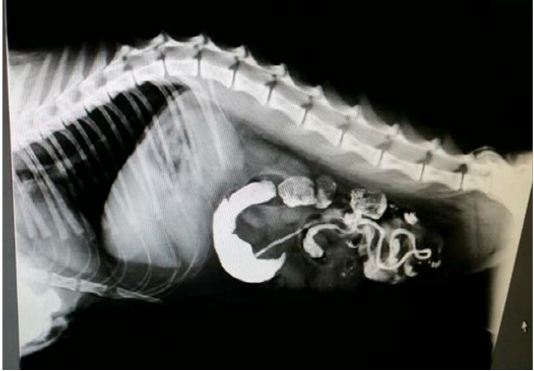

Figure 3

Lateral Radiograph after 33 hours of barium sulphate meal revealing accumulation of Barium in the intestinal loop and Barium has not passed into the rectum confirms intestinal obstruction